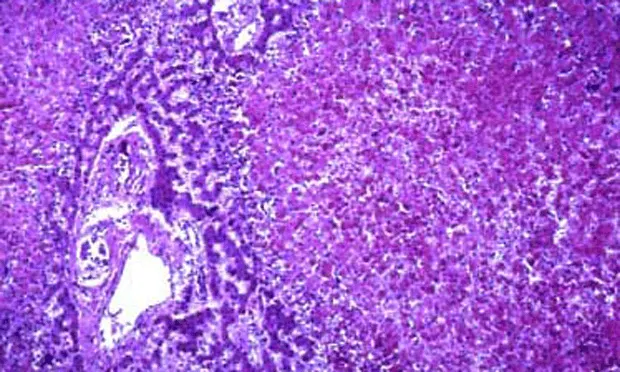

Determination of a primary liver disorder often relies on tissue sampling.

Neoplasia or hepatic lipidosis in cats may be diagnosed on cytology via fine-needle aspiration, but many primary disorders (particularly chronic inflammatory, fibrotic, or vascular diseases) require a histopathologic diagnosis, preferably from biopsy samples obtained via laparoscopy.21

Hepatic fine-needle aspiration and/or biopsy (preferably via laparoscopy)21